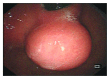

Aims: To review the clinical presentation, diagnosis, assessment of risk of malignancy, and recent advances in management (mainly focusing on the role of endoscopic resection) of gastrointestinal stromal tumors (GISTs) in upper GI.

Findings: The improvement of endoscopic techniques in treating upper gastrointestinal subepithelial tumors especially gastrointestinal tumors has reduced the need for invasive surgery in patients unfit for surgery. Many studies have concluded that modified endoscopic treatments are effective and safe. These treatments permit minimal tissue resection, better dissection control, and high rates of en bloc resection with an acceptable rate of complications.